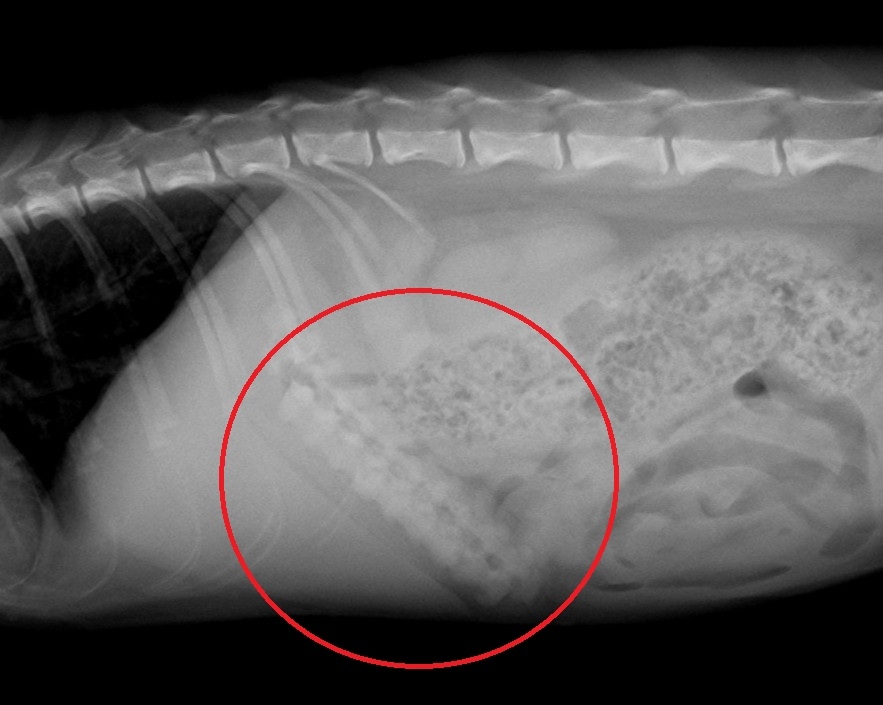

紹介されて、当院で撮影したレントゲンがこちらです。

赤丸印のところに棒状の異物が数本確認できました。